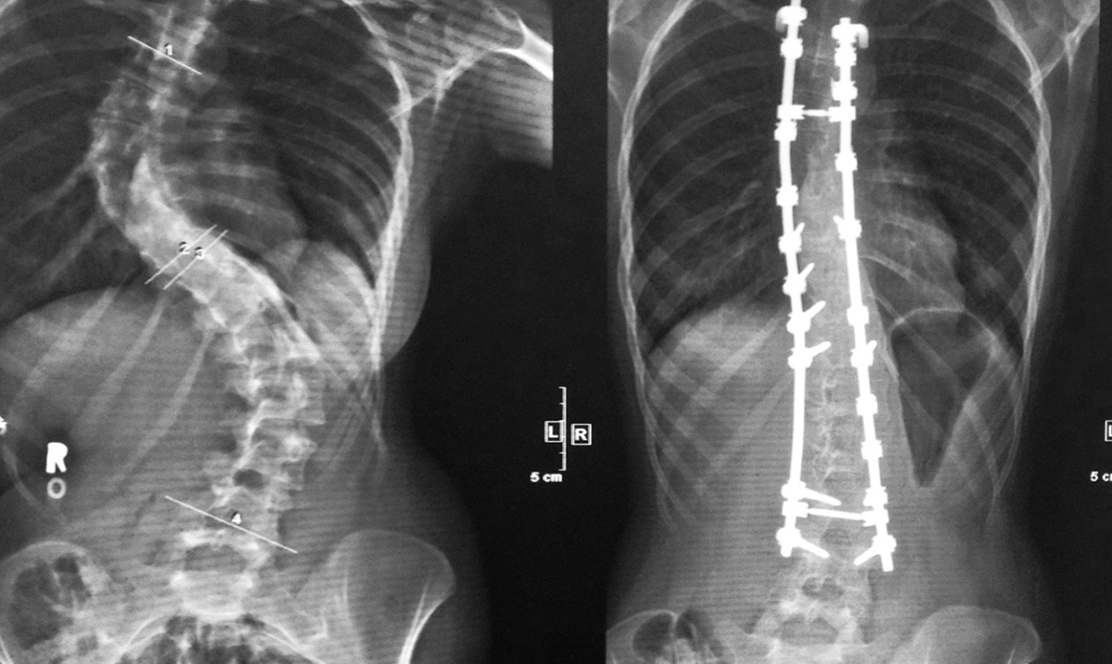

16 Year Old Girl With Right Thoracic Scoliosis A The Preoperative Download Scientific Diagram

A 14 Year Old Boy With Right Thoracic Scoliosis With Right Shoulder Download Scientific Diagram

A Q Male 14 Year Old Dysmorphic Scoliosis Surgical Treatment To Download Scientific Diagram